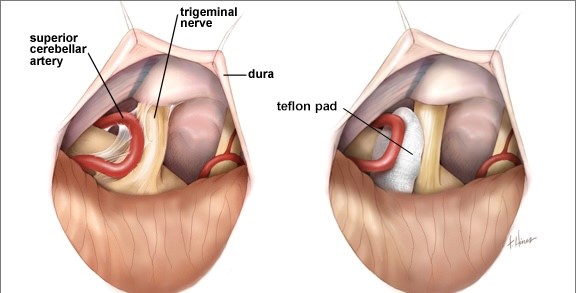

Vascular Neurosurgery

Our vascular neurosurgery program manages life-threatening and complex cerebrovascular conditions. Services include emergency intracranial bleed management with decompression and clot evacuation, treatment of arteriovenous malformations (AVMs) and arteriovenous fistulas (AV fistulas), and surgical clipping of brain aneurysms. All procedures are performed with meticulous planning and precision to minimize risk and preserve neurological function.